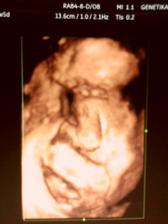

7.10.2009 nás čeká screening v 1. trimestru.*** Tak NT máme zdárně za sebou, nosní kůstka přítomna, NT 1,5 mm, CRL 7 cm i s nožičkama máme 11 cm, mimísek trochu ztěžoval pozorování, kroutil se do všech světových stran, srdíčko a všechny orgány se zdají být v pořádku. Výsledky krve budou až za týden :-/.***22.10.2009 - odběr krve na tripple test atd.., váha 59,2, UTZ bohužel neproběhl, za to jsem si vychutnala poslech srdíčka. A odpoledne konečně výsledky krve z NT - máme je v pořádku, riziko 1:12.900, huráá. Další kontrola na gyn. 20.11. - bude UTZ s vyloučením VV plodu a pak ve 21. týdnu USG srdce plodu u dr. Rušavé.***26.10.vystavena neschopenka, tripple test o.k. 🙂.***20.11. tak velký utz je v pořádku a mamka na vlastní oči viděla pindíka 🙂. Máme 356 g. Já váha 59,6. Další kontrola 16.12.***10.12.vyšetření srdíčka na dětské kardiologii, máme vše o.k. 🙂***14.12. 3/4D utz na genetice, vše je v pořádku, máme už 590 g a 30 cm, malej si dal hodně záležet na utajení vzhledu obličejíčku 😀, ale na DVD jsem ho v maličkej momentík nachytala.***5.1.2010 - test na cukrovku***13.1.2010 - kontrola na gyn., váha 64,5, na tvrdnutí břicha nasazeno magnézko polykací, hrdlo stále uzavřeno naštěstí..ale bohužel výsledky na cukrovku - pozitivní, hodnota na lačno 4,8, po 2 hod. 8,1, takže se musíme objednat na diabetologii :-/.***15.1. návštěva diabetologie, dostala jsem glukometr a 3 dny v týdnu si budu měřit, za 14 dní kontrola***28.1.utz ve 30.týdnu, vše o.k., máme 1761 g, hlavičkou dolů. ***17.2. kontrola, odběr krve, váha 67,2, další kontrola 1.3.***1.3. první natáčení na monitor, vše o.k., váha 67,8. Další kontrola 10.3.***10.3. monitor o.k., chvíli malej chrupkal, ale za chvíli si zas jel svoje tempíčko🙂, váha 68,8. Dnes mi byla ukončena PN a začala MD. Další kontrola 18.3.***monitor o.k., váha 70,2, začíná se projevovat zadržování vody v těle - už od rána nateklý kotníky a ruce, snubák už radši nenosim. Další kontrola 25.3.***25.3. na monitoru na křivce stahů první obloučky, něco se začíná dít?? Váha zase 70,2. Další kontrola 1.4.***Monitor v pořádku, váha 71,3. Další kontrola už bude v porodnici dne 7.4. ráno, tašku mít radši s sebou :-O...